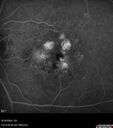

77 year old female HPI: CC: Decreased Vision OU. Since Last Visit: worsening. Location: central vision. Context nset/Aggravation: while reading. Modifying Factors: when closes one of her eyes notices letters are missing. Duration of Problem: couple of months. Associated Symptoms: foggy circle temporal when driving OU. Severity: moderate. Course: intermittent . HPI obtained by Steven M. Cohen, MD, FACS Medical Hx: Hypertension, Systemic. Hyperlipidemia. Depression. Spinal Stenosis. Psoriasis. Osteopenia Systemic Meds: TIZANIDINE HCL. TRAMADOL HCL prn. ZOLPIDEM. HYDROCORTISONE. TRAZODONE HCL, Clobex 0.05 % Topical Spray. VA OD 20/32, OS 20/20 IOP 13 OU